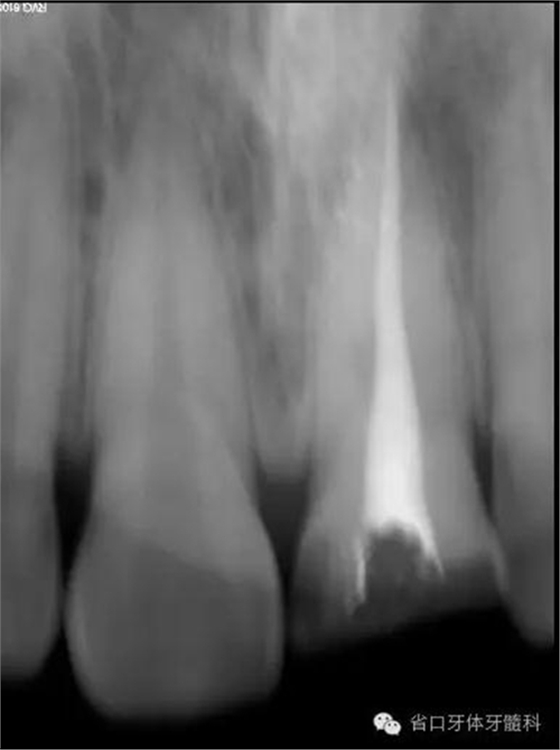

0.9%生理鹽水沖洗,吸潮紙尖干燥,連續(xù)波熱牙膠充填,拍片示21恰填。

根充后X線片